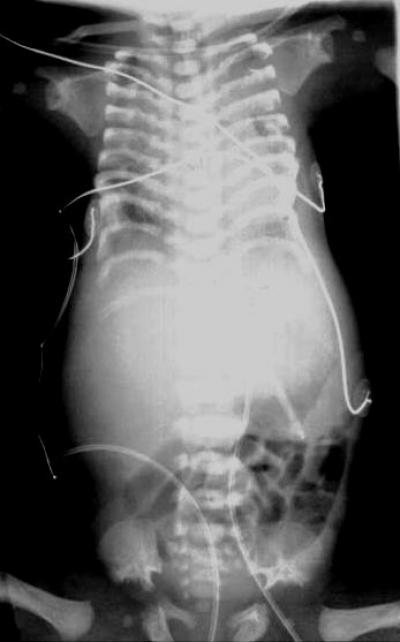

Many things go awry in short-rib polydactyly syndrome. The fetus develops extra fingers and toes and its skeleton doesn't grow, resulting in stunted ribs that prevent the lungs from maturing in the womb. Unable to breathe on its own, the child dies shortly after birth.